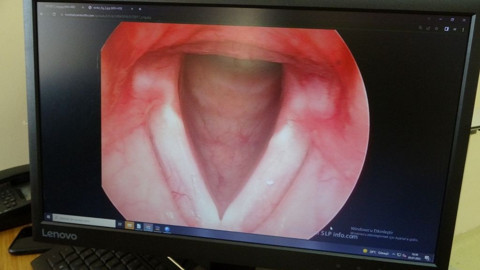

Galerinin tamamı için tıklayınızÖzellikle kadınların ses tellerinde daha çok etki gösteren sigara, önlem alınmadığı veya içmeye devam edildiği takdirde tehlikeli sonuçlara gebe olabiliyor.

Özellikle kadınların ses tellerinde daha çok etki gösteren sigara, önlem alınmadığı veya içmeye devam edildiği takdirde tehlikeli sonuçlara gebe olabiliyor.